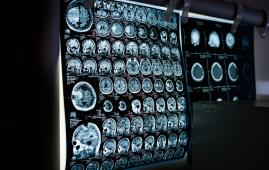

Huntington’s disease (HD) is a genetic neurodegenerative disorder that progressively impairs movement, cognition, and behavior. However, a recent study led by researchers at University College London reveals that subtle brain changes begin as early as 20 years before clinical motor symptoms appear. These findings could revolutionize Huntington’s prevention strategies and early treatments for Huntington’s and other neurodegenerative diseases.

Over five years, 57 participants with Huntington’s gene expansion showed no noticeable clinical decline in cognition or movement but exhibited progressive changes in brain scans and spinal fluid biomarkers. - Mechanistic Discovery: